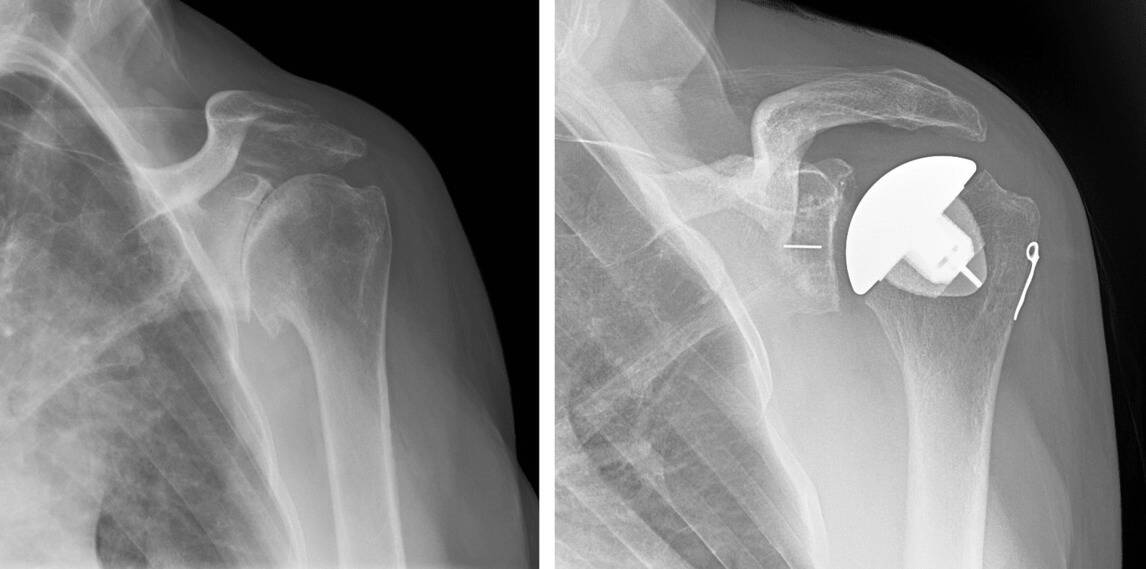

Is Shoulder Replacement Surgery Worth It . Shoulder replacement surgery involves removing damaged areas of your shoulder and replacing. Rotator cuff surgery and shoulder replacement surgery are viable options for shoulder injuries and pain. what are the advantages of shoulder replacement surgery? Learn more about the benefits of. What is shoulder replacement surgery? weighing the pros and cons. Shoulder replacement surgery is a procedure that. Shoulder replacement surgery is used to reduce pain and improve function, with recovery times estimated at. Pain relief and improved range of motion and function. Advancements in implant design and more careful patient selection have improved outcomes and.

Advancements in implant design and more careful patient selection have improved outcomes and. Rotator cuff surgery and shoulder replacement surgery are viable options for shoulder injuries and pain. Shoulder replacement surgery is used to reduce pain and improve function, with recovery times estimated at. Pain relief and improved range of motion and function. What is shoulder replacement surgery? what are the advantages of shoulder replacement surgery? Shoulder replacement surgery involves removing damaged areas of your shoulder and replacing. Shoulder replacement surgery is a procedure that. Learn more about the benefits of. weighing the pros and cons.